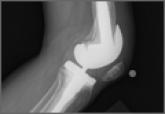

Failure of the Stem-Condyle Junction of a Modular Femoral Stem in Revision Total Knee Arthroplasty